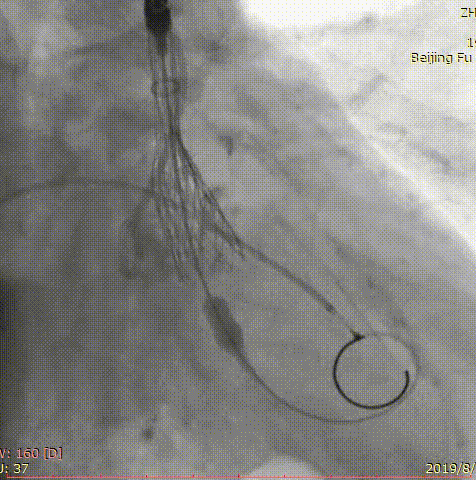

第三位患者是一位84岁女性,因间断头晕伴气短2年,加重1年入院,超声心动图提示主动脉瓣重度狭窄,左室壁肥厚,节段性室壁运动减低,主动脉瓣平均跨瓣压差91mmHg,收缩期流速 m/s,瓣口面积 0.6cm2。患者合并房颤、慢性肾功能不全、贫血。完善CT检查,测得主动脉瓣环 21*25mm,周长71.3mm,面积399.2mm2,患者三叶瓣,钙化分布较均匀,结合瓣上多平面分析方法,选择经左侧股动脉,应用微创心通 20*40mm敖广球囊预扩张,并成功植入Vitaflow 24mm主动脉瓣膜。术后超声提示收缩期流速1.7m/s,较术前明显下降。

术前影像